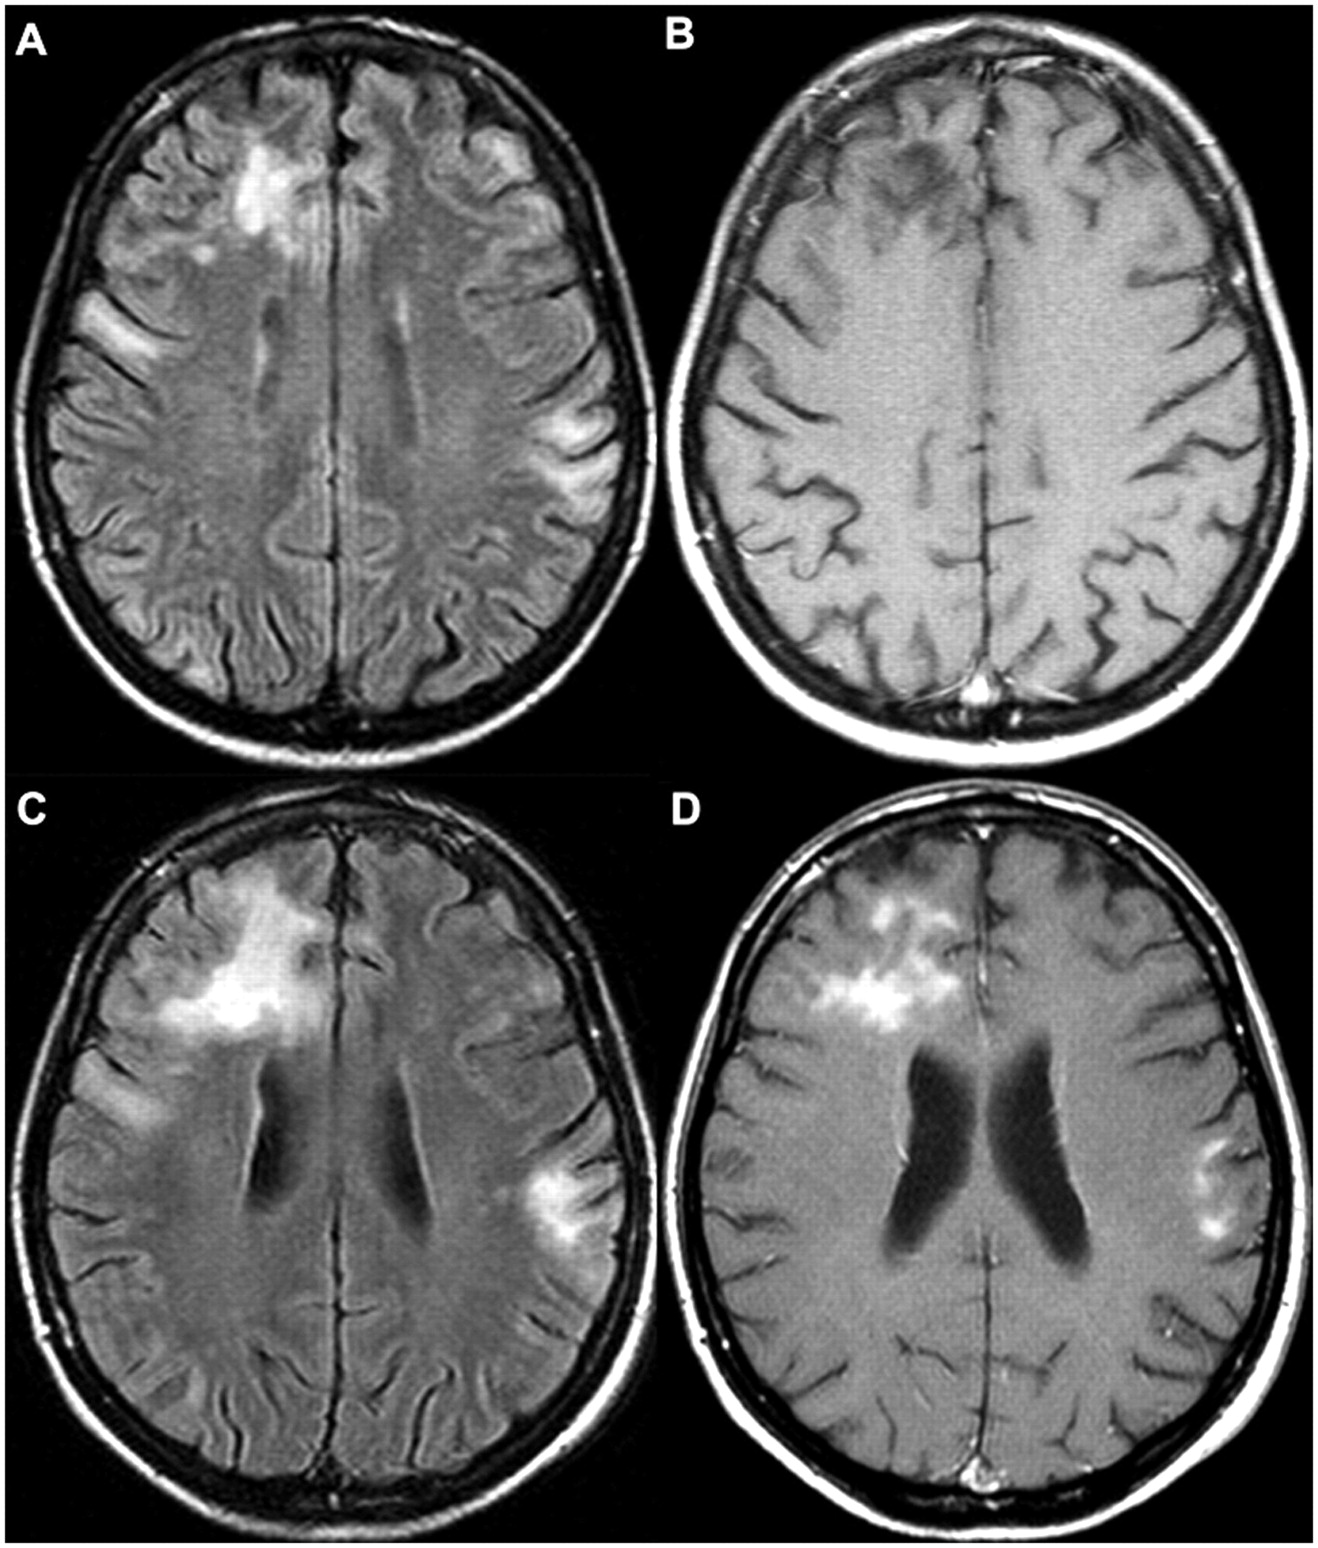

- Магнитно-резонансная томография позволяет обнаружить опухоли и другие аномалии в мозге.

| Диагностика | Неврологический осмотр, МРТ или КТ головного мозга, УЗДГ сосудов головы и шеи, лабораторные анализы (липидный профиль, глюкоза). | Точная диагностика позволяет своевременно начать лечение и улучшить прогноз. |